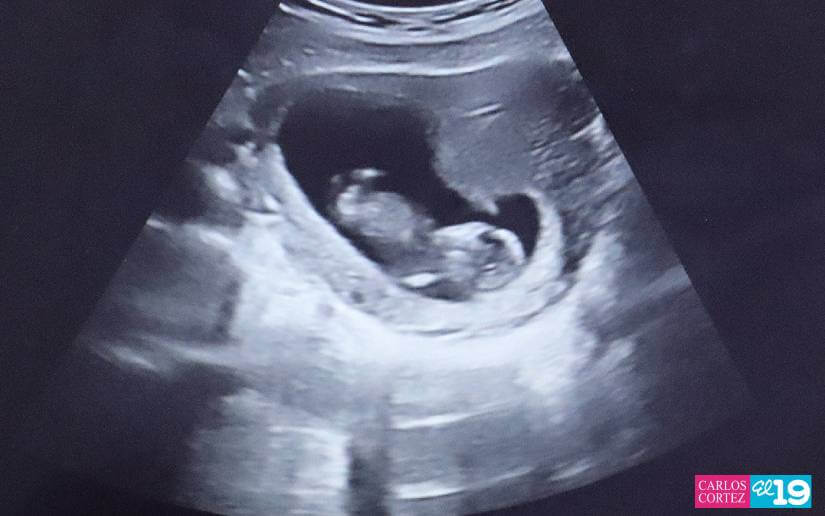

Durante la jornada, las pacientes no solo recibieron ultrasonidos, sino también una evaluación integral que incluyó la toma de signos vitales, medición de peso, talla y cálculo del índice de masa corporal. Además, se impartieron charlas sobre nutrición y se brindó atención especializada a mujeres con antecedentes de enfermedades crónicas como diabetes e hipertensión.

A quienes presentaron antecedentes clínicos se les realizó consulta médica y se les entregaron los medicamentos necesarios. Posteriormente, se efectuaron ultrasonidos correspondientes al tamizaje del primer trimestre, que se realiza entre las semanas 11 y 13 con 6 días de gestación.

“Estos estudios permiten calcular la edad gestacional del bebé y evaluar el riesgo de malformaciones congénitas, partos prematuros y desarrollo de preeclampsia”, agregó la doctora García.